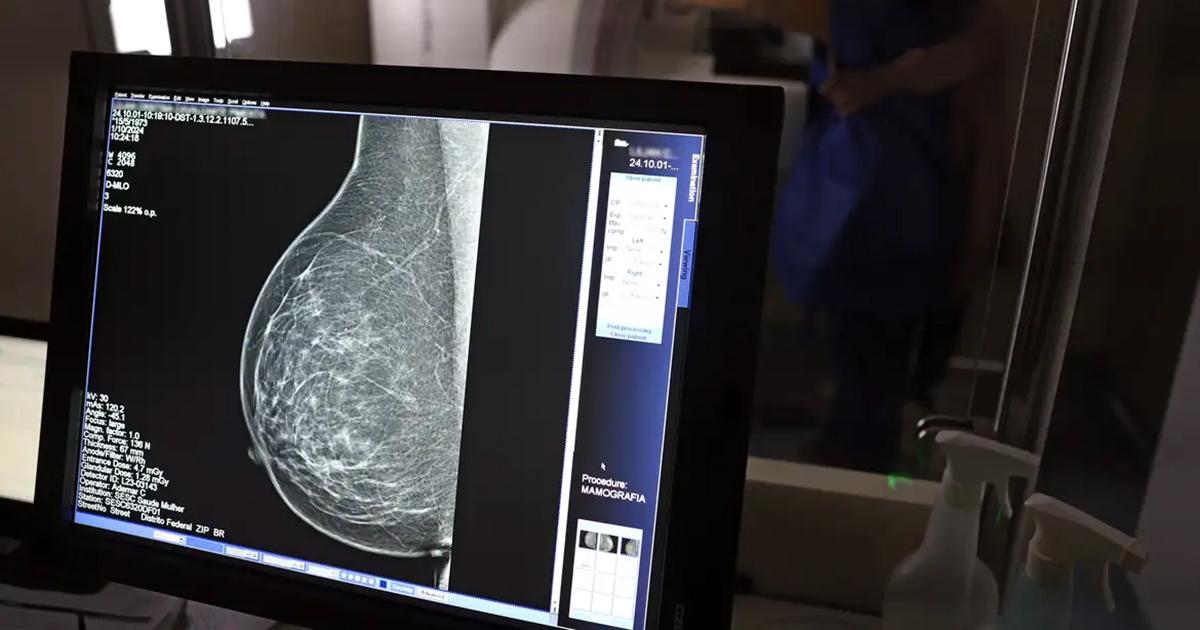

O Ministério da Saúde anunciou, nesta terça-feira (23), uma mudança histórica na política de prevenção ao câncer de mama que terá impacto direto no atendimento à população feminina de Santa Isabel. Mulheres na faixa etária de 40 a 49 anos agora poderão solicitar a mamografia pelo Sistema Único de Saúde (SUS) mesmo sem apresentar sinais, sintomas ou histórico familiar da doença.

A decisão, formalizada pelo ministro Alexandre Padilha, quebra uma barreira antiga na rede pública. Até então, mulheres nessa faixa etária, que concentra 23% dos novos casos de câncer de mama, frequentemente enfrentavam dificuldades para conseguir o exame preventivo. A nova diretriz estabelece que a solicitação do exame será uma demanda da paciente, em decisão conjunta com o profissional de saúde da Atenção Primária, após receber orientação sobre os benefícios e riscos do rastreamento.

Para as moradoras de Santa Isabel, a medida significa que o acesso ao diagnóstico precoce, fator crucial para aumentar as chances de cura, será ampliado na rede municipal de saúde. A expectativa é que a nova regra facilite o encaminhamento para o exame, que antes dependia de uma avaliação de risco mais restritiva.